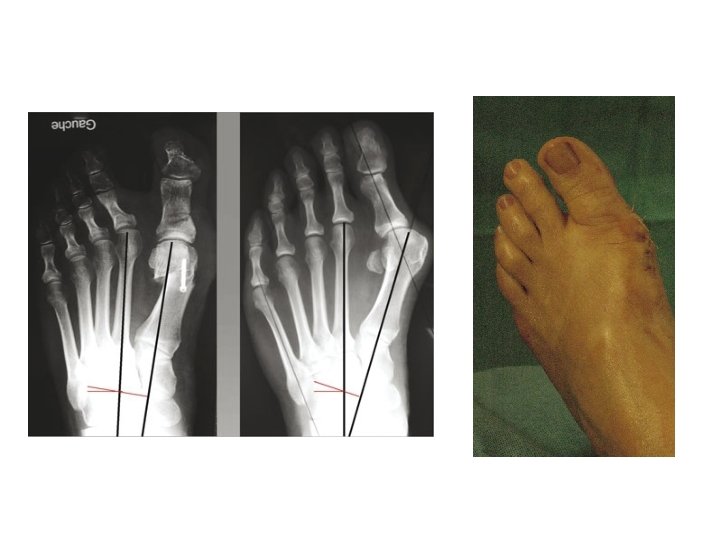

DIAGNOSTIC • Clinique: facile • Radiologique: éliminer une arthrose qui nécessiterait une arthrodèse (prothèses

DIAGNOSTIC • Clinique: facile • Radiologique: éliminer une arthrose qui nécessiterait une arthrodèse (prothèses peu utilisées car sources de nombreuses complications)

OSTEOTOMIE DU 1 ER METATARSIEN